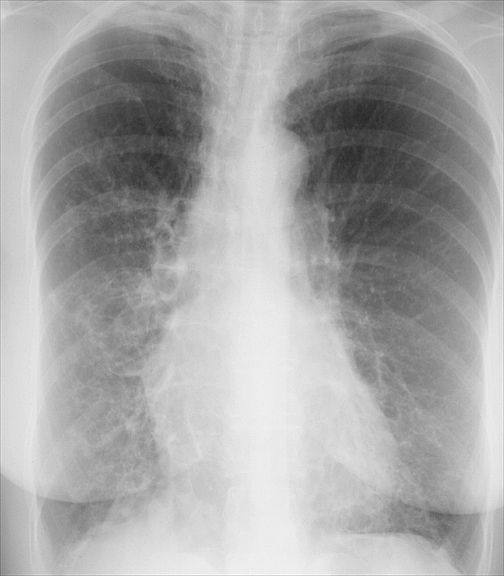

Bronchiectasis

Case 5 PA